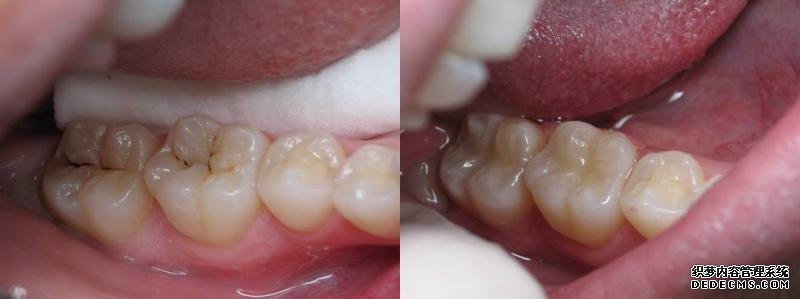

恒牙有虫牙怎么办?

一旦恒牙长了虫牙,就更应及时补牙了,这是因为恒牙一旦脱落了是无法再生的,另外,虫牙是一种破坏性的进行性疾病,不通过补牙是无法治愈的,而且虫牙不及时治疗,拖的时间越久,补牙难度越大。当虫牙导致牙体严重酸蚀缺损后,会直接侵袭牙髓或根尖周,导致剧烈牙疼,夜晚更甚,且伴有阵发性加剧的症状,这时有可能需要先进行根管治疗,清空髓腔和根管内的坏死物质再进行补牙填充,这样不仅增加了治疗难度、治疗费用,而且治疗时间也会延长。根管治疗通常需要2-4次才能完成。